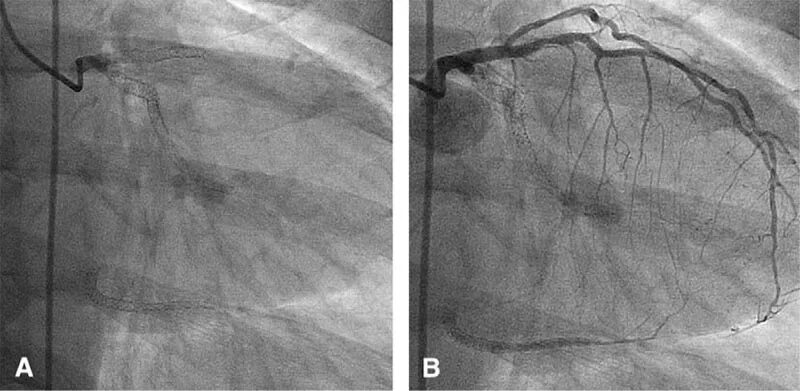

Шунтирование сердца и стентирование